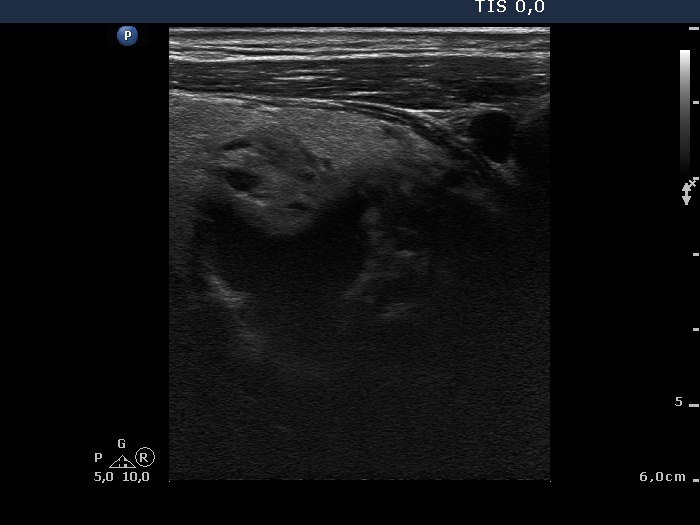

Ultrasonography: The thyroid was echonormal with a few insignificant lesions. There was a large cystic lesion dorsal to the lower third of the right lobe.

After aspiration of 10 ml yellow fluid the size of the lesion decreased from 35x31x42 mm to 29x22x39 mm. The patient refused to aspirate more fluid because her complaints ended.